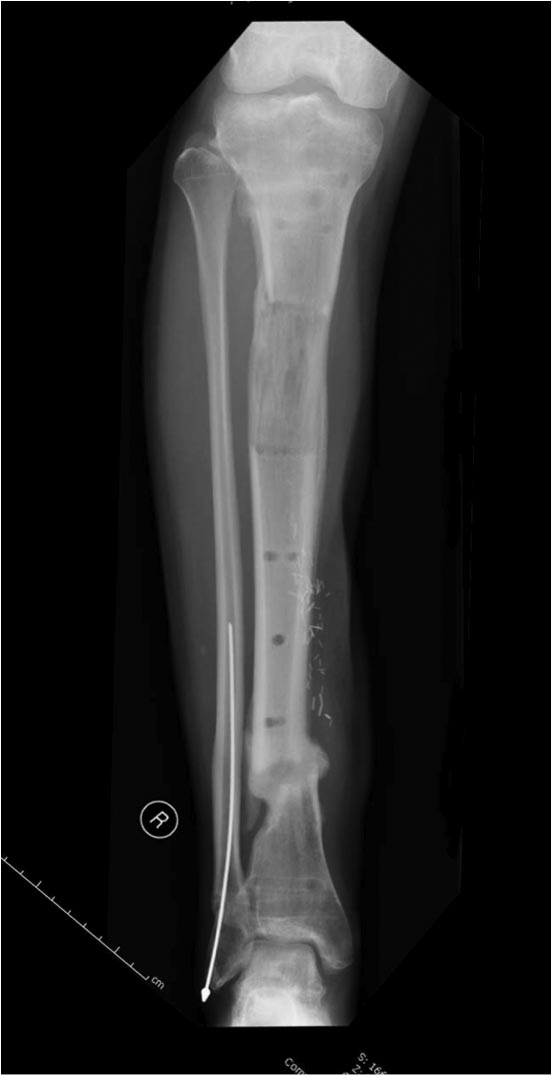

Здравствуйте уважаемые коллеги, прошу поделиться опытом лечения подобных повреждений-осложнений. Пациент Б. 40 лет, поступил в клинику 6.11.19 с огнестрельным переломом н/3 правого бедра и повреждением магистральных сосудов. Произведена ПХО ран, стабилизация перелома(с укорочением на 5 см.)стержневым АВФ, шов сосудов конец в конец. К сожалению, неверная выжидательная тактика привела к нагноению раны(Kl.pneumoniae).22.11.19 Этапная ХО раны, перемонтаж АВФ по типу-гибрид, удаление девитализированных костных фрагментов, депонирование дефекта бусами-спейсерами (амикацин-ванкомицин),VAC, Тигацил 100 мг.сут.26.11, 29.11, 3.12-этапные ХО с заменой бус и VAC,бак.посевы(возбудитель присутствует) . Макроскопически рана очистилась, гранулирует, однако имеется воспаление вокруг стержней. t. тела-в пределах нормы, лейкоциты снизились с 9,5 до 6.3, СОЭ с 62 до 31,СРБ с 98 до 49,гемогробин-98.Какую тактику применить на данном этапе?1 Masquelet с конверсией на гвоздь(пластину) с антибиотиком.2Аппаратное лечение с транспортом кости.3Другие возможные варианты.Заранее благодарю за помощь.

А воспаление вокруг стержней происходит из-за того, что на бедре мягкие ткани более мобильные, и возле нестабильных стержней образуется реактивное воспаление. Если не лечить, тогда воспаление может перейти в глубокие слои, а в данном случае (fat necrosis), т.е. локальный некроз, который лечится обработкой и созданием стабильности.

В данное время нет подтверждающих признаков распространения инфекции по медуллярному каналу, а также отсутствует данные, что повторная хирургическая обработка может повлиять на процесс образования тромбоза.